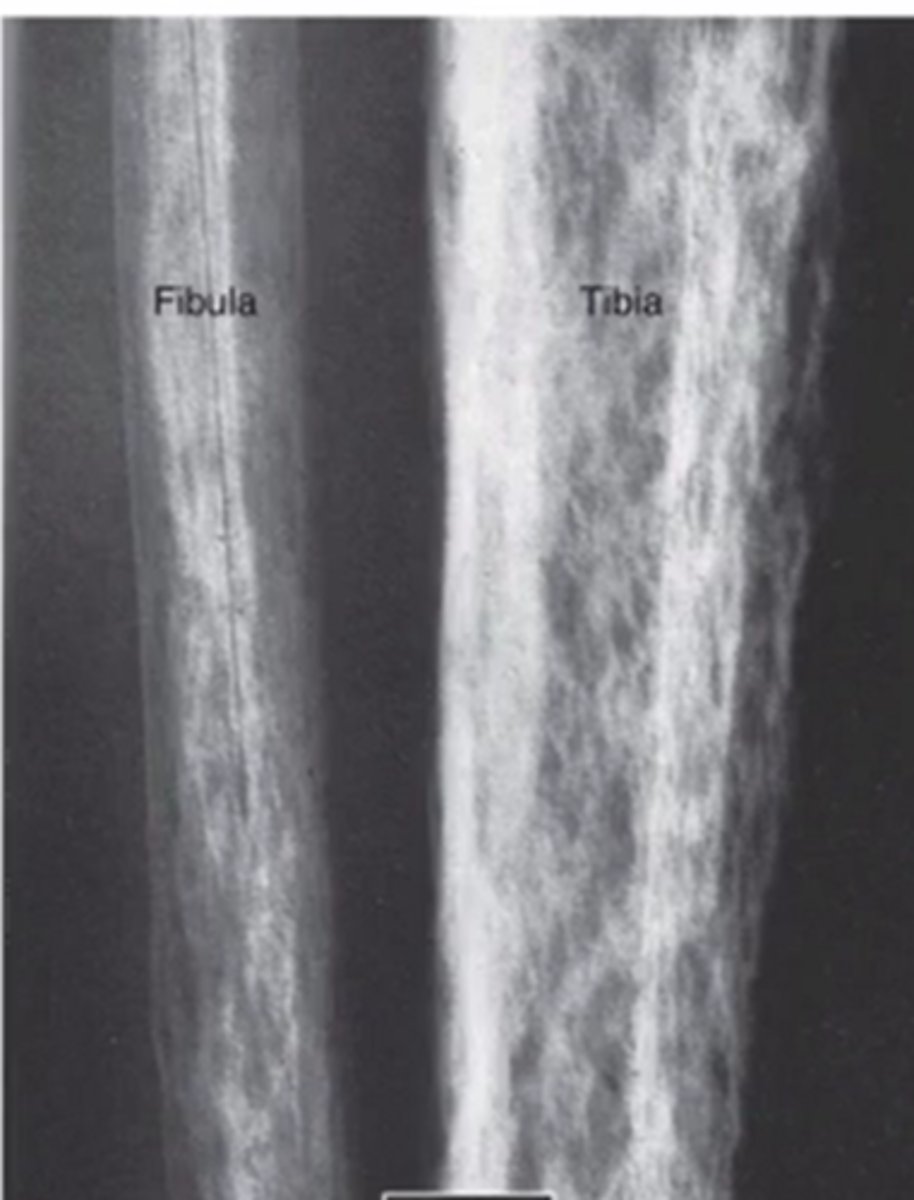

what does a trabeculae abnormality look like

what is sclerosis as it relates to bone

increase in bone density